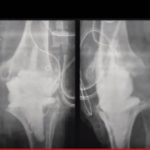

Current trends in Hand infection Management

Courtesy: Dr. David Fuller, MD, Associate Professor and Program Director of Orthopaedic Surgery, Cooper Medical School

Saqib Rehman MD, Director of Orthopaedic Trauma, Temple University,Philadelphia, USA